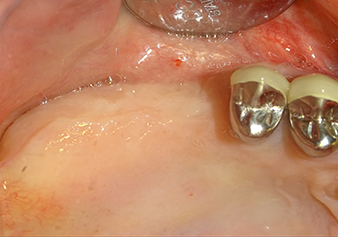

Для перемещения аугментационного материала в направлении верхнечелюстной пазухи атравматично, имплантат вводился очень медленно вручную (рис. 9). При этом мембрана еще раз выталкивалась в краниальном направлении. Через два месяца место операции зажило без раздражения. Через шесть месяцев рентгеновский контроль показал значительное увеличение помутнения, что свидетельствует об оссификации (рис. 10). Протезирование было проведено металлокерамической коронкой.